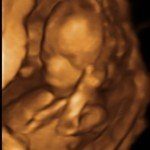

4D/5D/HD Ultrasound Gallery

Gallery